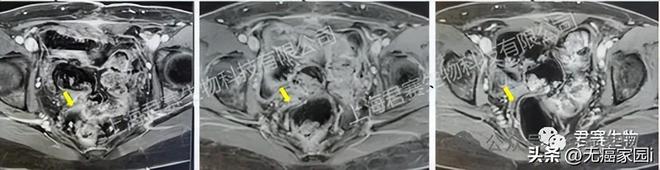

受试者接受TIL回输前、回输后6周及回输后12周影像资料(图源官网,侵删)